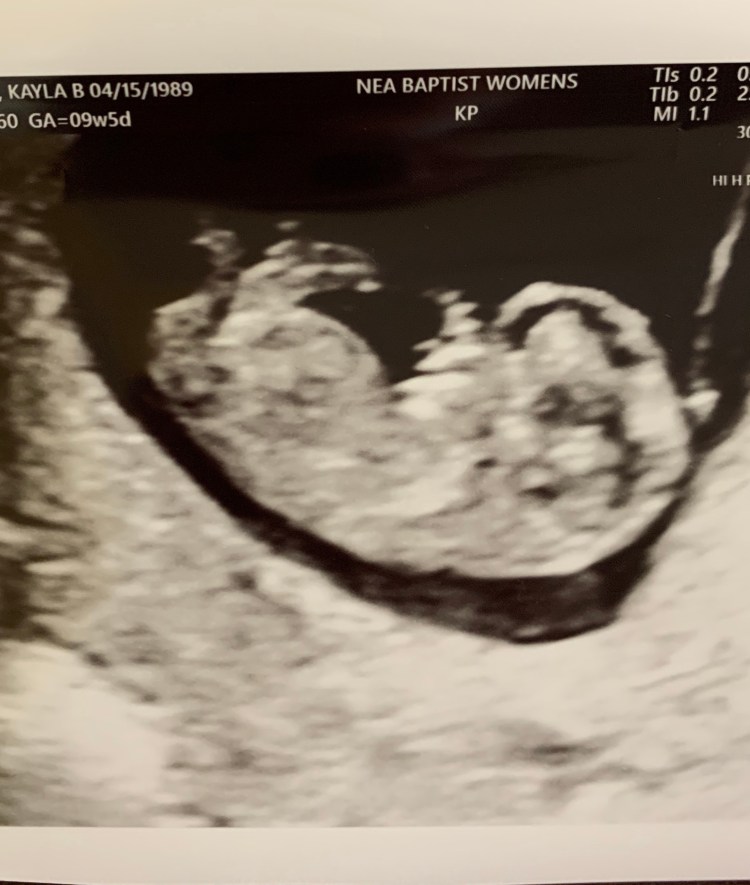

Exactly a year and a day after Andrew’s vasectomy we found out Baby Rowlett #5 would be joining us! We are over the moon excited about this baby and we have so much faith that God has such an amazing plan for his life! The kids are also REALLY excited! The twins have been asking for another baby for quite some time now. They are so excited to have another baby to love on and play with! Rhett is also extra happy to be having a brother!